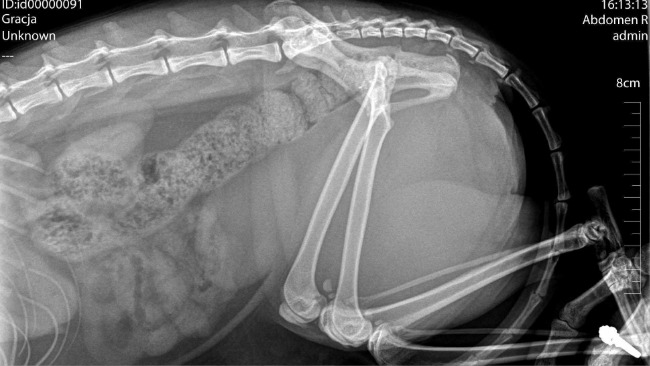

Kotka zaczęła mieć problem z oddawaniem stolca, finalnie przestała się wypróżniać. Kolejne wizyty w lecznicach, jedna nawet w godzinach nocnych ujawniły podejrzenie ciała obcego w jamie brzusznej. Zaczęto podejrzewać również chłoniaka.

Podjęto więc decyzję o niezbędnym zabiegu. Grację trzeba było "otworzyć", aby potwierdzić diagnozę - jedną lub drugą. Wcześniejsze badania RTG i USG niestety nie dały jednoznacznej odpowiedzi.

Szczęście w nieszczęściu - okazało się, że Gracja ma w przewodzie pokarmowym ogromny bezoar - zbitek włosów.